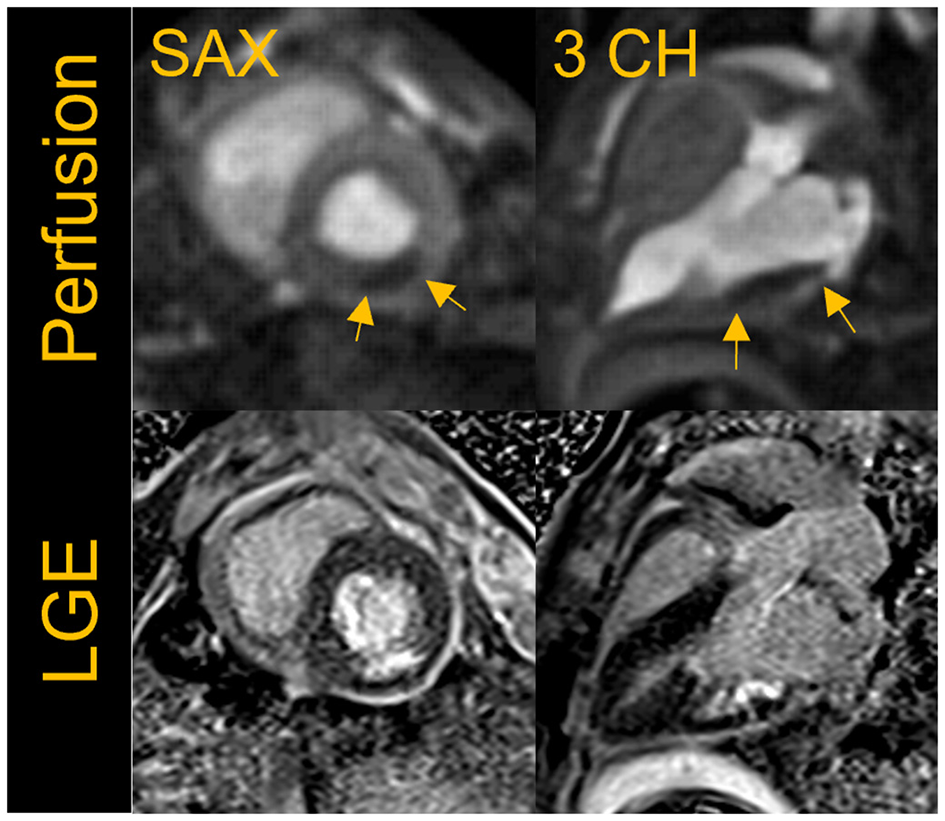

Figure 7 shows an example of resting perfusion images indicating a perfusion defect in a region of known myocardial infarction. The perfusion images acquired in healthy volunteers were determined to have visually comparable image quality to that of the animal studies. Further work is needed to quantitatively assess the perfusion defects and to validate the technique across different B0 systems. The results shown were acquired using state-of-the art image reconstruction technology developed in-house, and fast computer hardware to achieve highly accelerated real-time cine and perfusion imaging with rapid, in-line reconstruction. While such technology is not widely available currently, our preliminary results represent a promising pathway toward global realization of these CMR techniques.

Figure 7

First-pass perfusion images acquired at rest with a fat suppressed, saturation-recovery T1-weighted gradient echo (GRE) sequence shows rest perfusion defect in the short-axis (SAX) and three- chamber view in a porcine infarct model where the left circumflex artery was occluded. The images shown here were acquired ~5 weeks post-myocardial infarction (MI). The perfusion defect visually correlates well to the region of infarct as seen in the corresponding breath-held segmented late gadolinium enhancement (LGE) images.